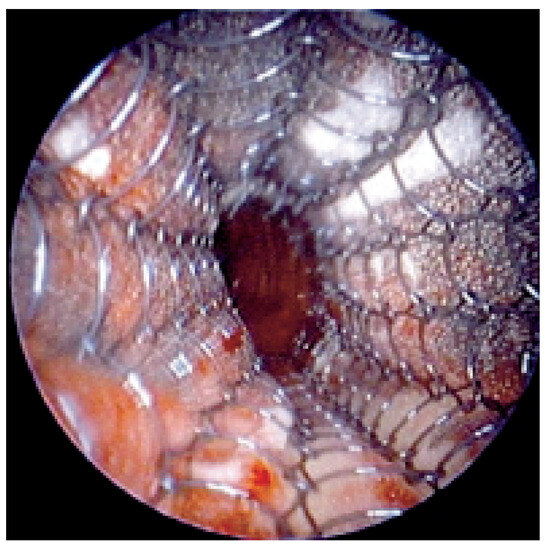

Endobronchiales Stenting

by Felix J. F. Herth and Ralf Eberhardt

Patients with lung cancer often have bulky endobronchial disease, endobronchial extension, or airway compression. Many endobronchial treatment modalities are available to supplement traditional therapies for advanced lung cancer. Since the early 1980s, technical advances in interventional techniques have enhanced symptom-free survival and quality [...] Read more.

Patients with lung cancer often have bulky endobronchial disease, endobronchial extension, or airway compression. Many endobronchial treatment modalities are available to supplement traditional therapies for advanced lung cancer. Since the early 1980s, technical advances in interventional techniques have enhanced symptom-free survival and quality of life for patients with lung cancer. Although interventional procedures are not definitive therapies, they often relieve the strangling sensation produced by airway occlusion. For patients with respiratory symptoms associated with their disease, the stent placement provides symptom palliation and improves quality of life. The author reviews the use of several available endobronchial stents. Full article

Show Figures

Figure 1